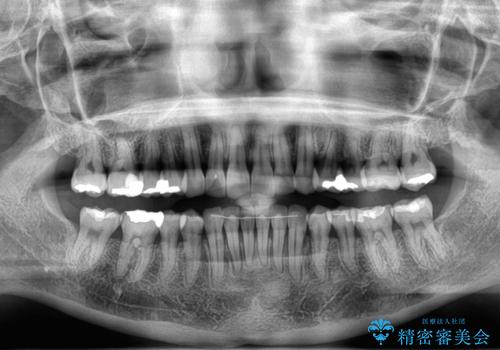

- 前歯のディープバイトと叢生を気にして来院された患者様です。

目立ちにくい装置を希望されていたため、ワイヤー装置とインビザラインを提案したところ、インビザラインを希望されました。

下顎大臼歯が手前に倒れていたため、起き上がらせることで咬み合わせ高さを挙上し、ディープバイトと叢生を改善することとしました。

インビザライン特有の奥歯の噛みにくさが治療後半に発言しましたが、無事に終了させることができました。